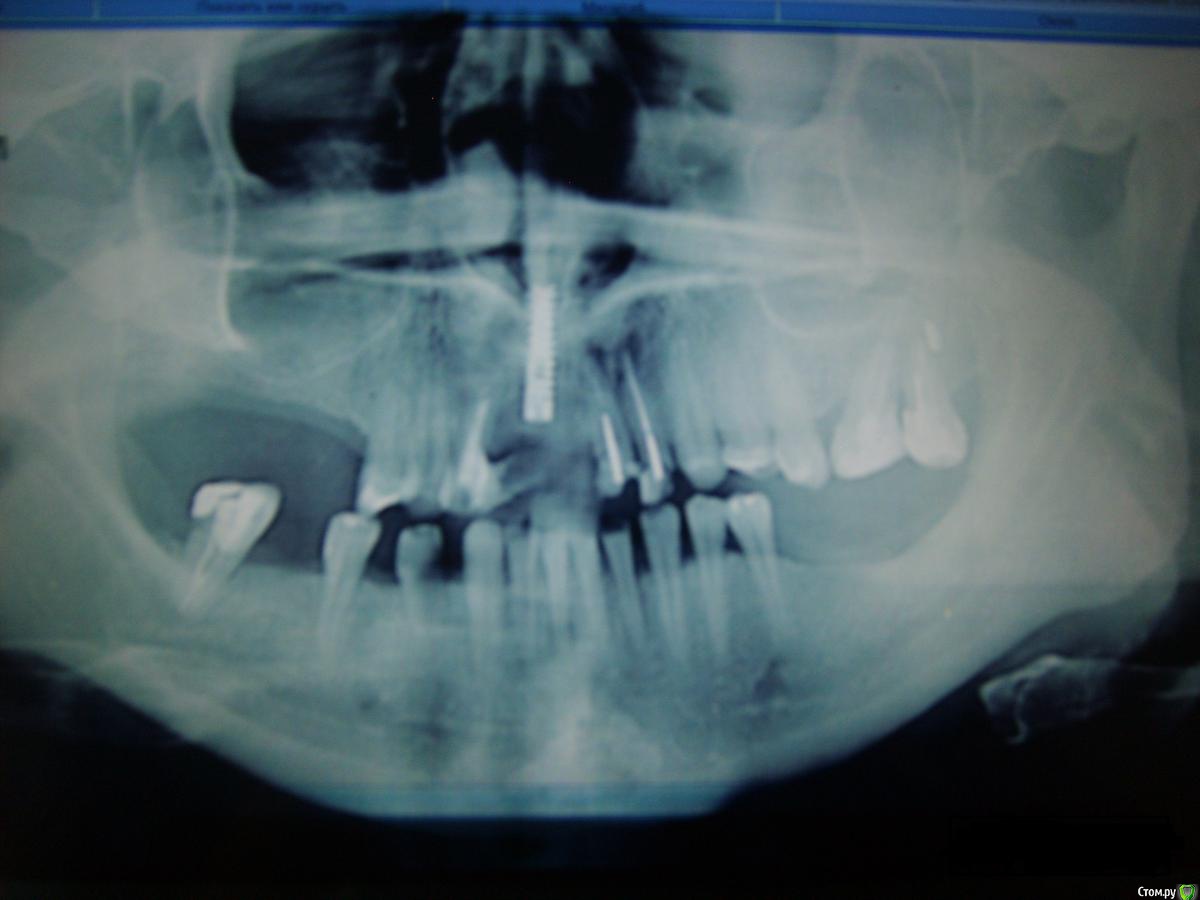

Masha4 Опубликовано 27 декабря, 2015 Поделиться Опубликовано 27 декабря, 2015 (изменено) Уважаемые Эксперты, уважаемые Врачи, здравствуйте! Очень прошу Вашей помощи с планом операций, т. к. запуталась окончательно. В 2015 г. обратилась к хирургу (клиника №1) для комплексного решения своей непростой ситуации.План операции Доктор "озвучил" следующий:1 этап - операция. общий наркоз - РВК 21, 22; -лоскутная операция 25, 26, 27 -удаление импланта 11 -костная пластика 3 участка (забор из повздошной кости)2 этап - имплантация 8-9 едениц:3 этап - постоянное протезирование (через 4 мес.). По факту операции (май 2015г.) я получила:-удаление 12-костная пластика 4 участка ( зоны 12, 15-16-17, между "разъехавшимися" 45 - 46, 36-37-38). Слизистую щеки пришивали на десну.Имплант 11 оставили. Сказали он "стабилен", при постоянном протезировании установить коронку с искусственной десной. Июль 2015. Из импланта начал немного подтекать гной. Зона 11-12, периодически небольшое жжение,воспаление, дискомфорт. Доктор сказал что причина - 21.Про имплант 11 сказал что они его в мае попытались выкрутить, но не смогли. Когда он будет ставить импланты, удалит 11 и сразу же на его место установит другой. Костная пластика в этой зоне не нужна! (место позволяет установить другой) В двух других клиниках (клиника №2, №3) сказали - причина все-таки имплант 11, т.к. вокруг него полость. В настоящее время, Хирург, делавший ОП, настаивает на операции. Срочно. Иначе уйдет кость.За одну операцию(предмедикация-удаление 21, 22--имплантация 8-9 единиц (21,22,12, 11(по ситуации), 15, 16, 17, 36, 37, 38, между 45 и 46)-если получится! - удаление импланта.( План в бумажном варианте не составляется. По фронту Доктор сказал: пока не вскроешь - не поймешь. Но импланты на жевательную группу установят 100% ) Клиники №2 и №3 рекомендуют следующий вариант:1. установить импланты на жевательную группу2. через 1-2 мес. заняться фронтом (за одну операцию)-удаление старого импланта 11-установка имлпанта 12-попытаться сделать РВК 21, 22.-если РВК не получится удаление-имплантация.3. в зоне 11 возможно, больше ничего не делать (живого места нет) При постоянном протезировании мост 21-12 на имплантах. Уважаемые Врачи,очень прошу Вашего заключения и оценки моей ситуации.Что бы Вы мне посоветовали, на что еще нужно обратить внимание?Очень Вам благодарна! Большое спасибо! Изменено 27 декабря, 2015 пользователем Masha4 Ссылка на комментарий

brg Опубликовано 27 декабря, 2015 Поделиться Опубликовано 27 декабря, 2015 Фото жуть, нормальные выкладывайте. Ссылка на комментарий

Masha4 Опубликовано 27 декабря, 2015 Автор Поделиться Опубликовано 27 декабря, 2015 Согласна. жуткая-жуть.Это на самом деле ужасно выглядит.Подскажите пожалуйста, нормальные фото - это с другого ракурса? Как лучше сделать? Ссылка на комментарий